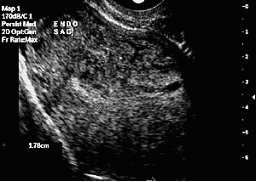

Преди сонохистерография |

След сонохистерография |

Матката ясно се разпознава с вагиналния ултразвук.

Инжектирането на солеви разтвор в маточната кухина раздалечава двете страни на ендометриума и подобрява визуализацията на някои структури, като напр. полипите. В допълнение, солевият разтвор служи за контрастно вещество, което позволява да се видят вътрематочни сраствания (синехии).